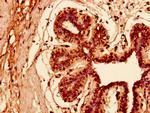

KRT81 Polyclonal Antibody

WB IHC (P) ELISA

货号 PA5-97914

Cytokeratin 81/86 Polyclonal Antibody

WB IHC (P)

货号 PA5-104293